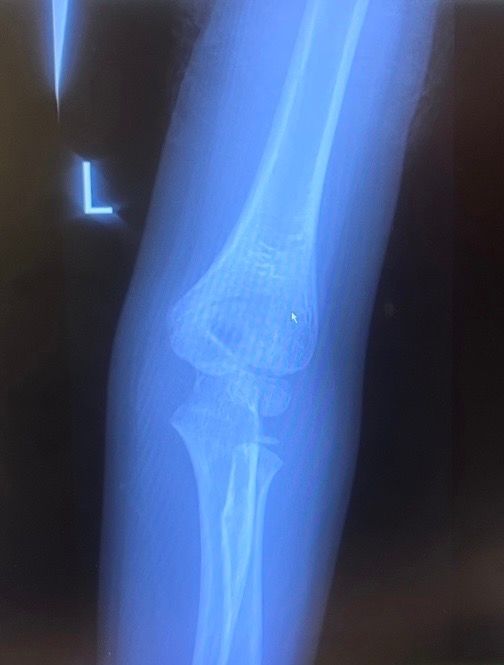

아이 팔꿈치 뼈 어긋남?? 수술 필요??

안녕하세요. 해외에 살고있는데요, 아이가 놀이터 미끄럼틀에서 떨어져 팔로 딛고 아파해서 응급실에 갔더니 팔꿈치 골절이 있고 뼈가 살짝 어긋났다고 하네요. 만약 어긋난게 돌아오지 않는다면 수술이 필요하다는데, 전문가님들 보시기에 뼈가 어긋나고 향후 수술까지도 생각해야하나요?ㅠ 7살 남아입니다

질문에 올린 사진각도만으로는 정확히 평가할수가 없습니다.

골절이 뚜렷하지 않아서 보여주신 X-ray 사진 한장만 가지고 판단하기 어렵습니다.

여러 각도로 찍었을텐데 같이 보여주셔야 판단이 가능하겠습니다.

그리고 소아에서는 뼈가 다 유합되지 않았기 때문에 반드시 양측 비교를 해서 골절 여부를 확인해야합니다.

골절선과 뼈의 유합선이 구분이 안되는 경우가 있기 때문입니다.